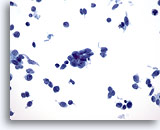

Lymph node FNA, atypical lymphoid proliferation.

The specimen is cellular and when compared to small lymphocyte a the majority of cells are slightly larger than this cell. The monotony of the sample is worrisome. 20x

Lymph node FNA, atypical lymphoid proliferation.

The specimen is cellular and when compared to a small lymphocyte the majority of cells are slightly larger than this cell. The monotony of the sample is worrisome.